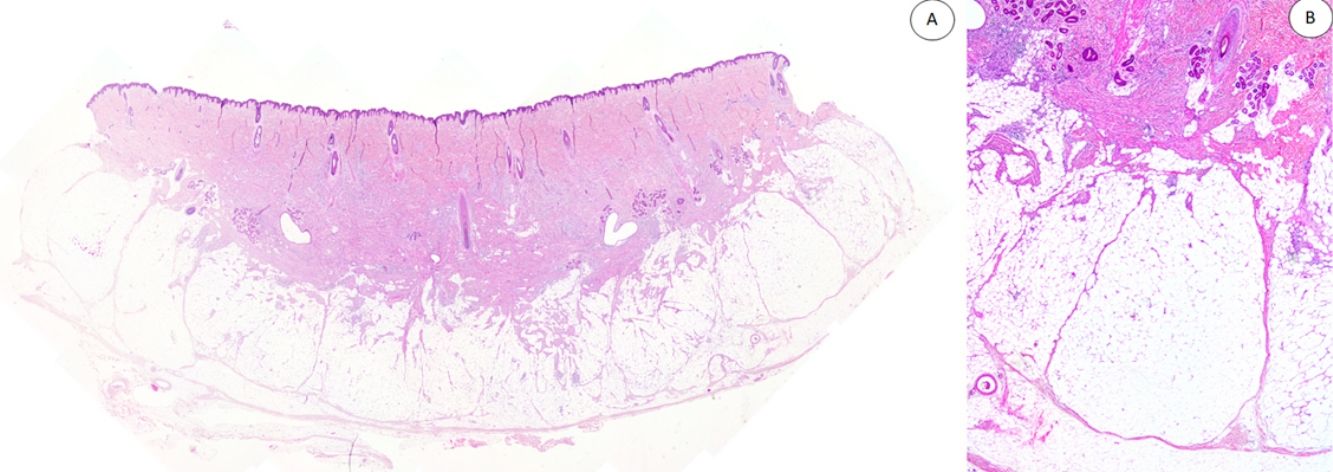

Los casos se caracterizaban por presentar una morfología trifásica con una proporción variable de tejido fibroblástico/miofibroblástico, mesenquimal inmaduro y adiposo maduro en dermis o subcutis (figs. 1, 2 y 3). En términos generales, las lesiones se describieron como mal delimitadas (fig. 1).

A) HFI dérmico e hipodérmico B) A mayor aumento, bandas densas de tejido fibroso proyectándose en el tejido graso maduro. C) Trabéculas entrelazadas de tejido fibroso que presentan colecciones de fibrocitos de aspecto inmaduro en patrones de espiral. D) Componente mesenquimatoso inmaduro basófilo entremezclado con tejido fibroso.

HFI: hamartoma fibroso de la infancia.

Las trabéculas fibrosas varían en grosor y disposición, y contienen haces de células en forma de huso dispersos aleatoriamente entre haces de colágeno (con colecciones de fibroblastos de aspecto inmaduro, formando patrones en espiral) (fig. 2). Los nódulos mixoides de tejido mesenquimal inmaduro estaban compuestos por células redondas o estrelladas primitivas, indiferenciadas, dispuestas libremente o embebidas en un estroma mixoide (fig. 3). Finalmente, podemos observar áreas de tejido adiposo maduro (figs. 1 y 2).